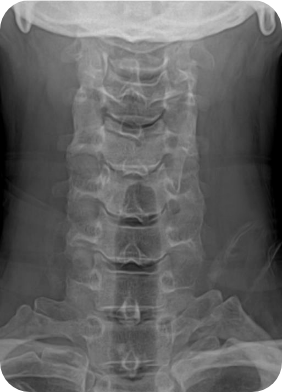

경추 전방,후방 추간공확장술은 해당 병변을 제거하고 나머지 디스크는 제거하지 않고 되도록 유지한 후 신경공만 넓혀주는 수술법입니다.

대개 목디스크 수술이라고 하면 경추 사이에 있는 디스크를 모두 제거하고 그 안에 인공뼈나 인공디스크를 삽입하여 인접부위에 문제를 야기시키기도 하는데, 이를 보완하여 그 마디를 유지하고 신경공만 넓혀주는 수술입니다. 경추와 흉추 사이에 디스크 발생시, 가슴 뼈가 수술부위를 가리는 경우 아주 유용하게 선택할 수 있는 방법입니다.